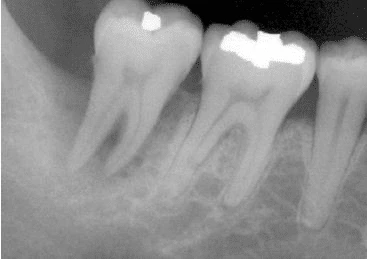

Hình 1. Phục hồi trong thân răng không khít sát có thể tạo áp lực lên răng và gây nứt dọc chân răng.